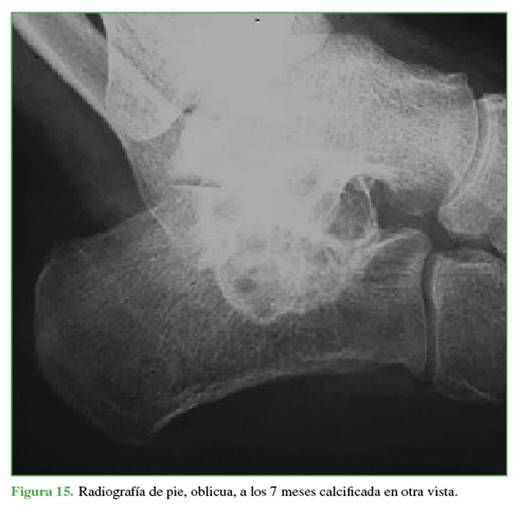

En los sucesivos controles clínicos y radiológicos, se comprobó la osificación de los quistes y la desaparición del dolor (Figuras 13-15). Después de más de 2 años de seguimiento, el paciente no ha vuelto a consultar. Como se sabe que el QOA puede recidivar, se debe mantener un control a más largo plazo.